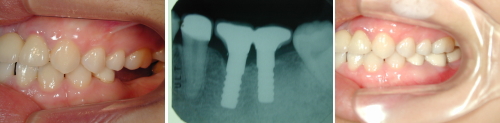

治療例を下記の通り示します。患者さんは20歳台後半で、診査の結果から歯周疾患にもまだ無縁と思われたため予知性の高いインプラントを植立して審美機能回復を図りました。もちろんブリッジでの機能回復も可能ではありますが、一番奥の歯を削られたくないという本人の強い希望を尊重しての処置となりました。

↑奥から2番目3番目がインプラントです

こちらの患者さんは40歳台の方で、上あごの一番奥を失ってしまい噛みにくいので歯を作って欲しいとの希望で来院されました。一本だけの入れ歯は嫌だということでインプラントを提案し処置を行いました。

↑1番奥の歯がインプラントです